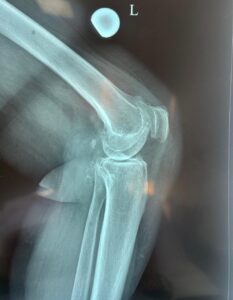

Ana Biriucov a fost operată la genunchiul stâng pe data de 6 martie. Pacienta spune că, în ultimii ani, durerile au devenit tot mai puternice, afectându-i serios activitățile zilnice.

În urma investigațiilor, medicii au stabilit diagnosticul de gonartroză de gradul III–IV, o afecțiune caracterizată prin uzura avansată a cartilajului genunchiului și îngustarea pronunțată a spațiului articular.

Intervenția chirurgicală a fost efectuată de echipa Secției Ortopedie Protetică a Articulațiilor Mari, condusă de șeful secției, Alexandru Bețișor. Potrivit medicului, pacienta a beneficiat de protezare parțială unicompartimentală a genunchiului, o procedură minim invazivă prin care este înlocuită doar partea articulației afectată de artroză. Tehnica permite păstrarea cartilajului sănătos și a ligamentelor încrucișate, ceea ce contribuie la menținerea unei mobilități mai naturale a genunchiului și la o recuperare mai rapidă.